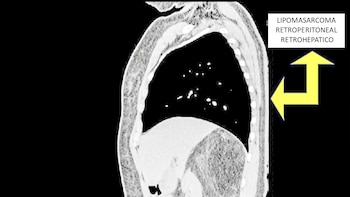

Ana Llacsaguache García, piurana de 41 años, experimentó un cambio radical en su vida tras someterse a una intervención de alta complejidad en el Hospital Nacional Almanzor Aguinaga Asenjo. Un equipo multidisciplinario logró extirparle un tumor maligno de aproximadamente cinco kilos, ubicado en la zona retroperitoneal y con un diámetro cercano a los 25 centímetros. Esta masa comprimía estructuras vitales entre el hígado y el riñón derecho, lo que ponía en riesgo inminente la vida de la paciente.

Durante tres años, la paciente soportó un dolor abdominal persistente que afectaba su rutina diaria y su bienestar general. Los síntomas, cada vez más intensos, motivaron su derivación al hospital de Essalud en Chiclayo, donde exámenes especializados confirmaron la presencia de un liposarcoma de grado 1.

La localización y el tamaño del tumor convertían la operación en un reto médico de máxima exigencia, ya que cualquier error podía comprometer órganos esenciales.

La cirugía, que se extendió por más de cinco horas, fue liderada por el jefe del Departamento de Cirugía, doctor Juan Rodríguez Terrones. El especialista detalló que la extracción requirió una técnica precisa, debido a la fuerte adherencia del tumor a órganos y vasos sanguíneos fundamentales.

“El mayor desafío fue retirarlo sin provocar daños colaterales que pusieran en peligro la recuperación de la paciente”, subrayó Rodríguez Terrones, poniendo en valor el trabajo coordinado y la pericia del equipo quirúrgico.